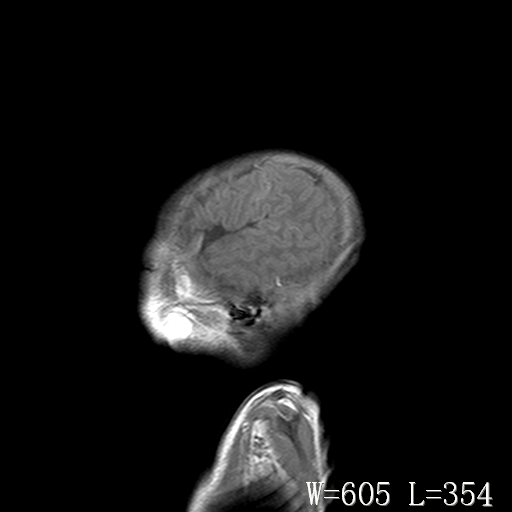

标题: PED3338:脑部病变?

男,4天,发复抽搐1天。

新生儿正常颅脑

脑干形态欠规则,信号增高,不知怎么解释?

脑干背侧面t1高信号是,新生儿正常已经髓鞘化好的部位